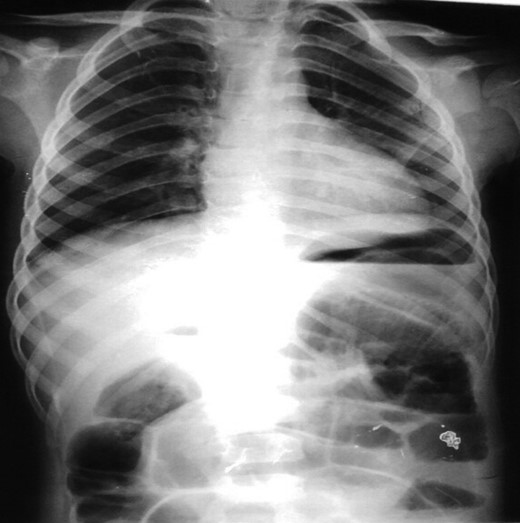

Through investigations, erect Abdominal X-RAY (AXR) showed air-fluid levels in the small bowel and dilated loops of the large bowel (Fig. 1).

Erect AXR showing Air-Fluid levels and distended large bowel loops.